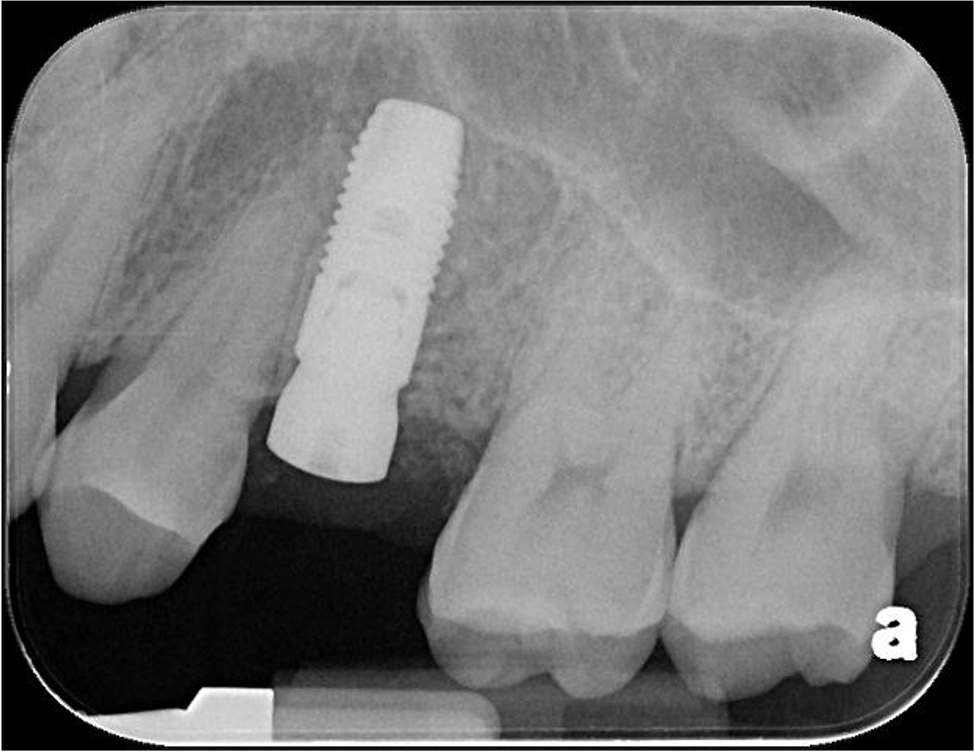

植牙後X光